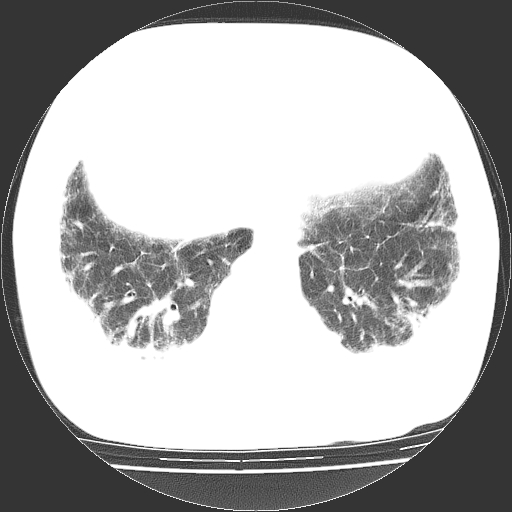

男,68岁,咳嗽、胸闷、发烧三天,查体:双肺散在湿罗音。

依据:1、两肺广泛条索状、网格状、蜂窝状改变。

双肺多发条索状、网格状及小灶状密度增高影。考虑慢支合并感染.间质纤维化,双侧少量胸腔积液

两肺广泛条索状、网格状、蜂窝状改变。肺间质纤维化,肺心病,双侧胸腔积液